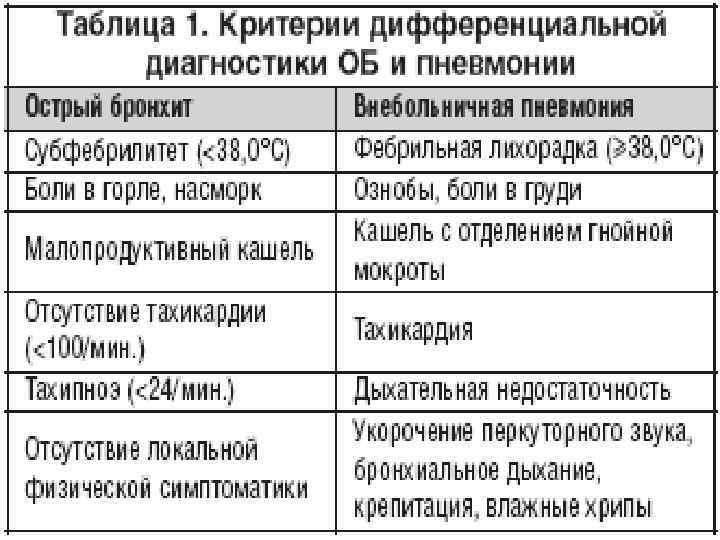

При проведении дифференциального диагноза пневмонии следует исключить другие заболевания, сопровождающиеся притуплением перкуторного звука при сравнительной перкуссии лёгких, кашлем и болями грудной клетки: острый бронхит, туберкулёз и рак лёгкого.